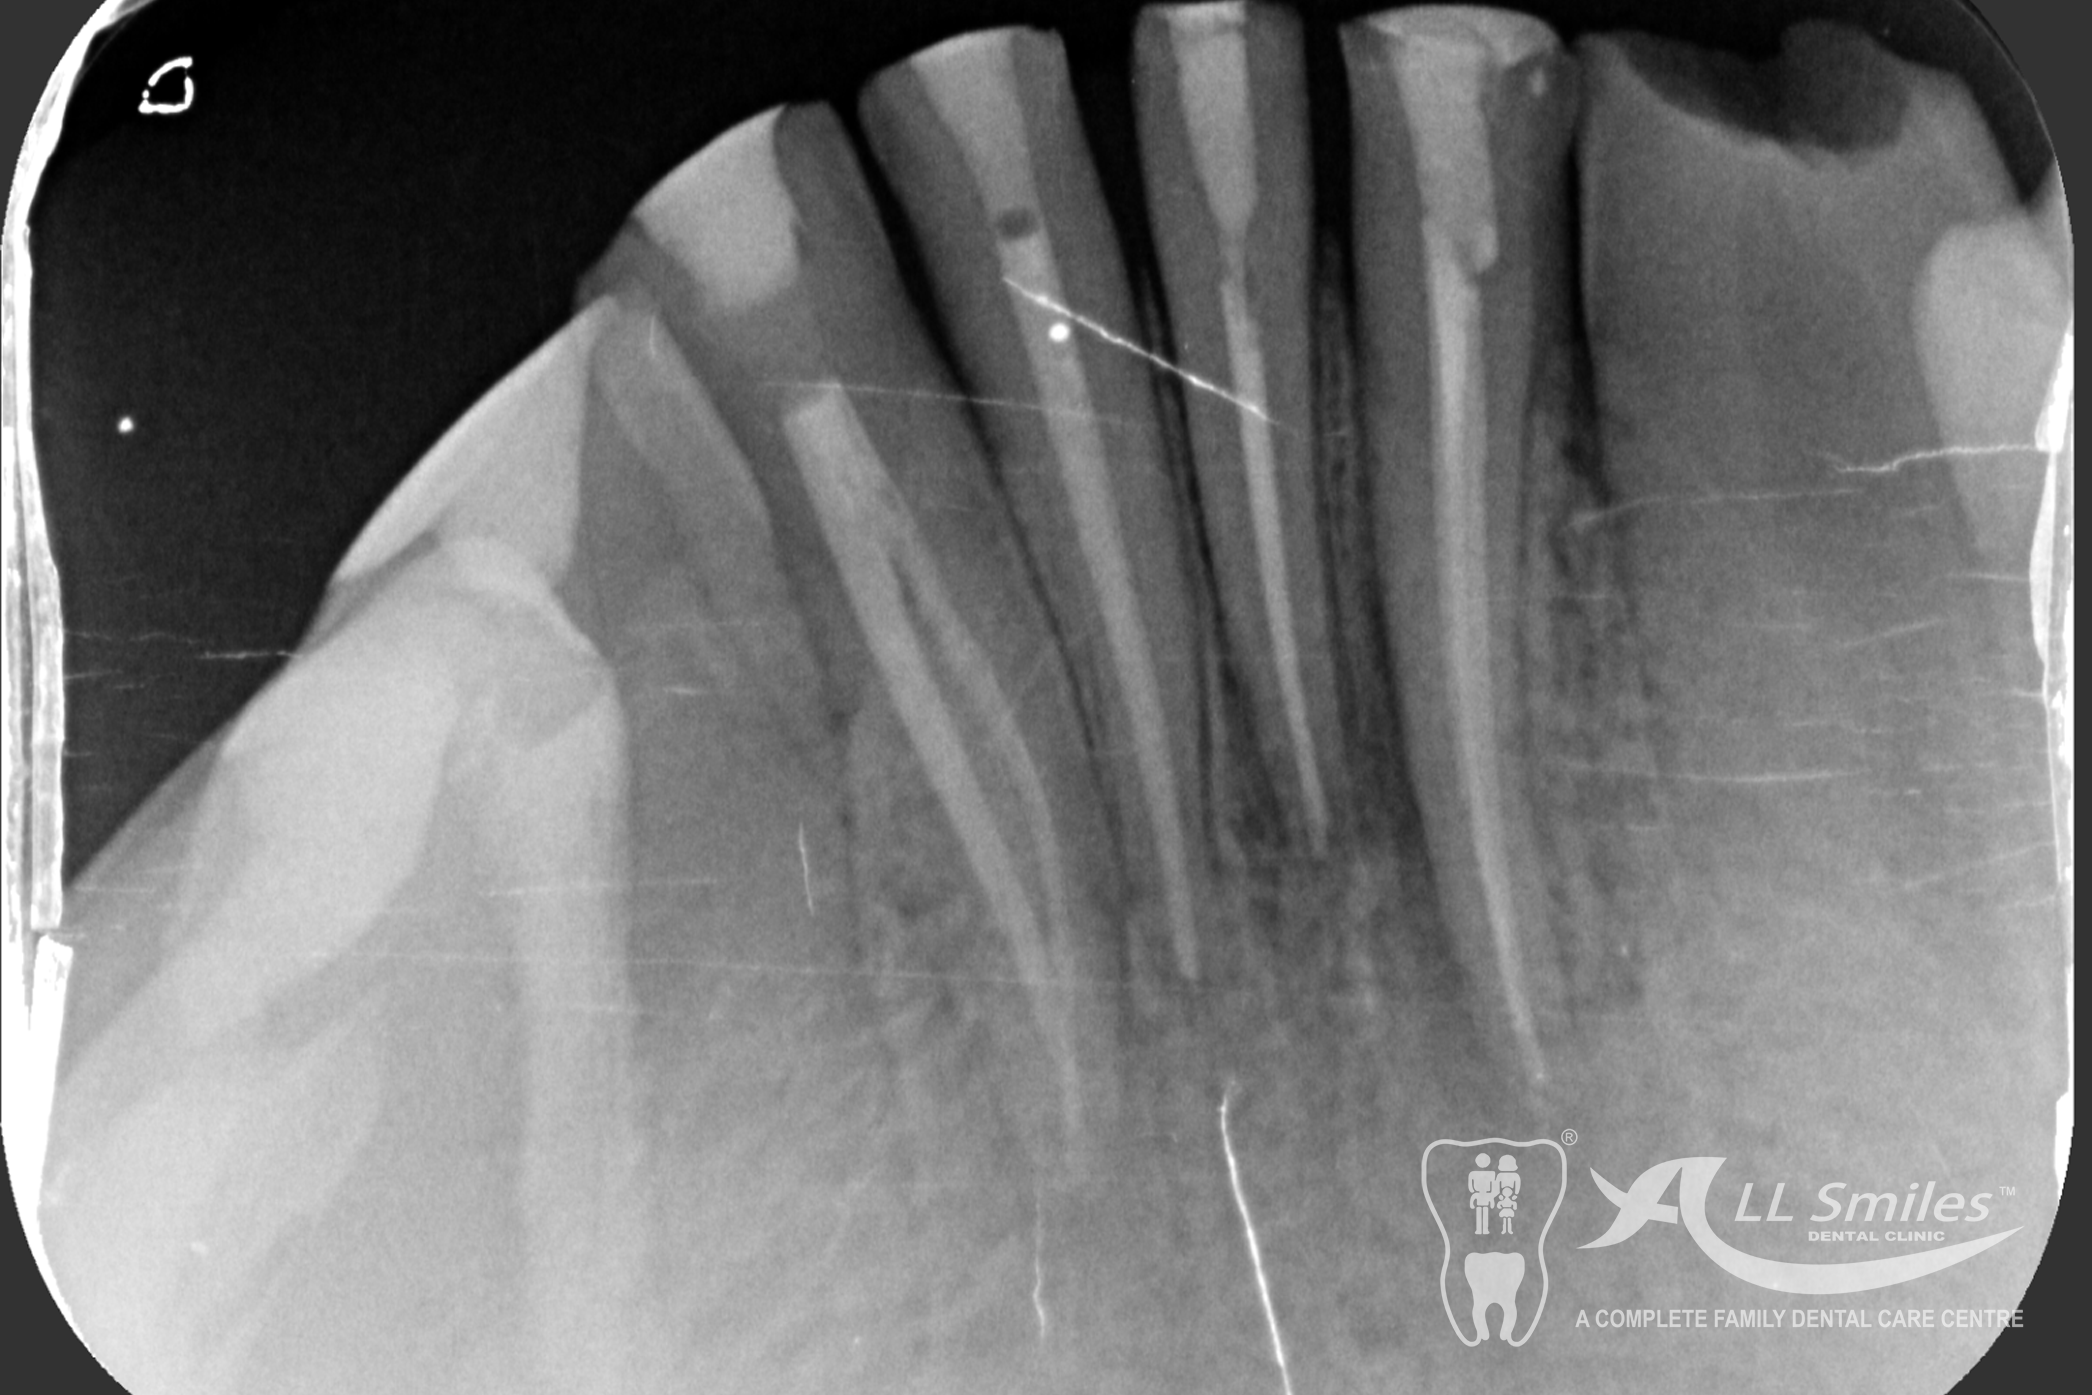

Root Canal Gallery